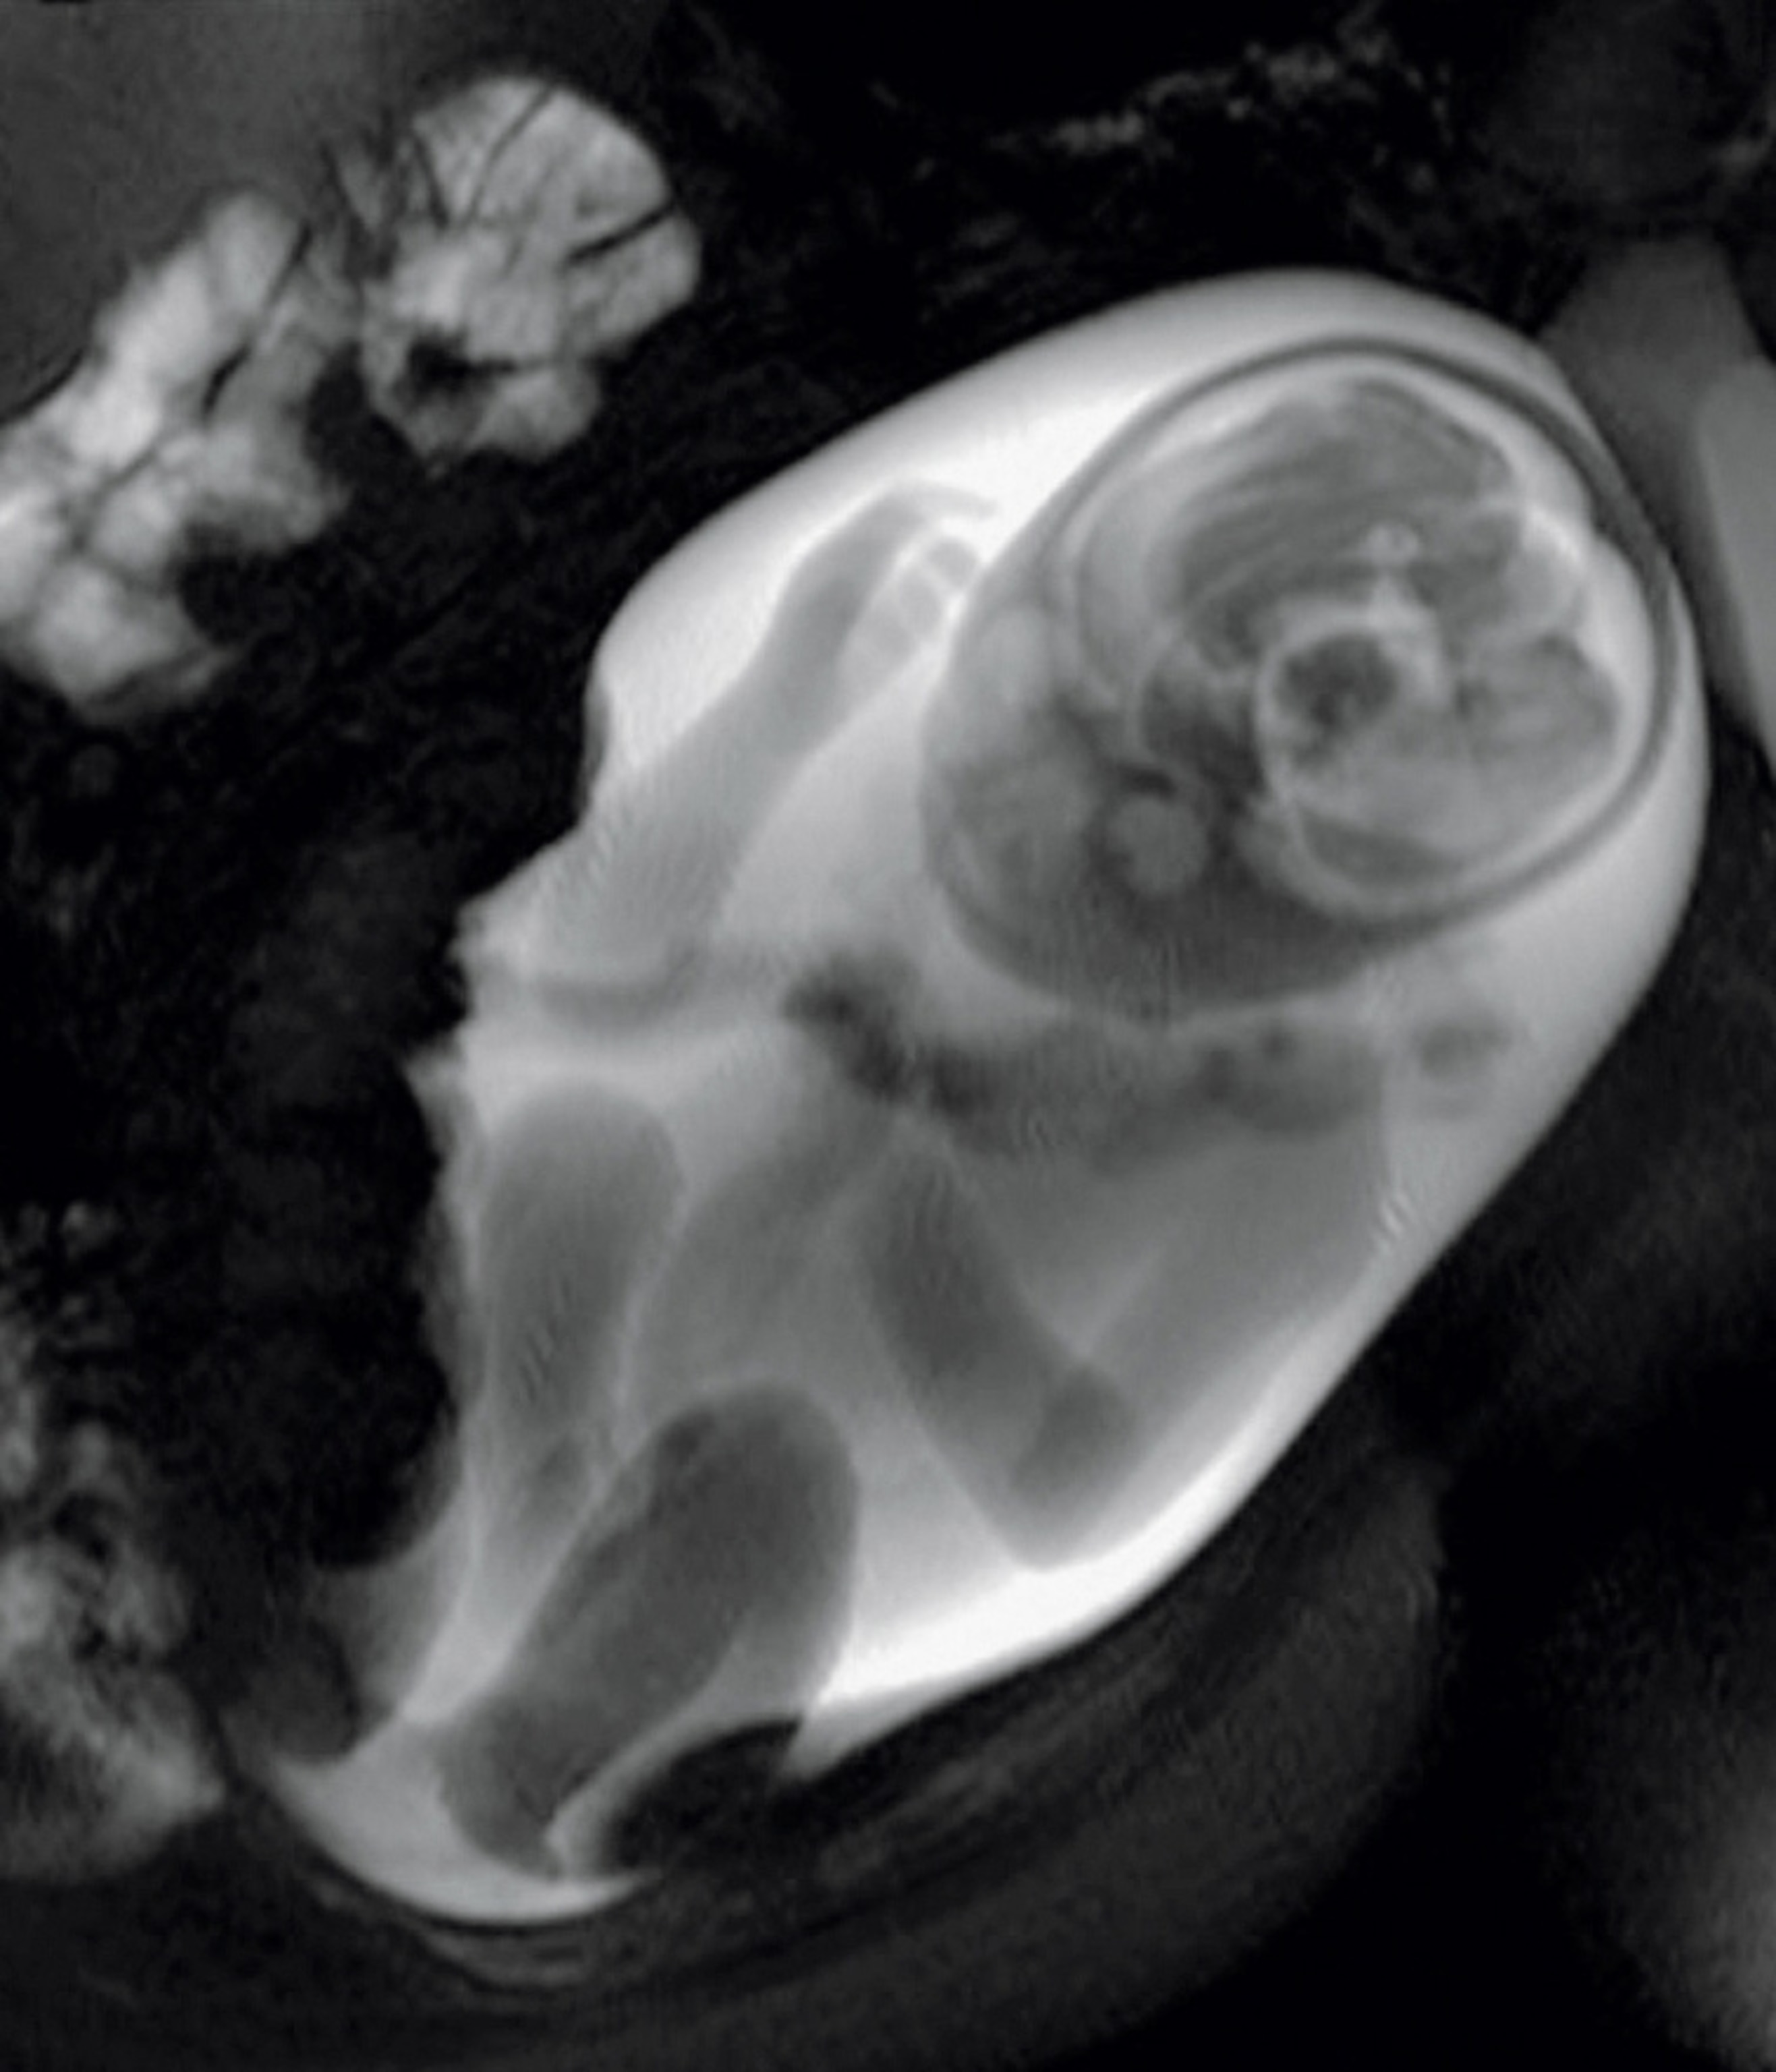

Diagnosis in utero is on the far horizon, says pediatric neuroscientist Moriah Thomason, whose research aims to solve some of the mysteries of the fetal brain. At Detroit’s Wayne State University, she and her team use MRI technology to check the growth of a fetus’s brain and map the neural connectivity within it, creating a groundbreaking snapshot of how well the organ is functioning.

They focus on cases where there’s danger of premature birth, Thomason says, because “we know that preterm children are at higher risk for developmental delays.” Such delays are often blamed on stress or lack of oxygen during birth. Thomason’s work suggests impairment may start in the womb, possibly with an undetected infection.